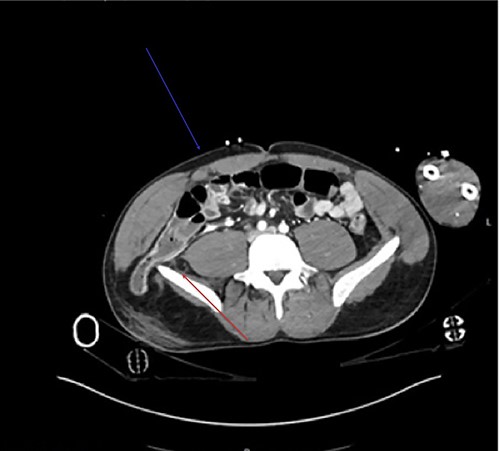

Sagittal view demonstrates the inferior lumbar hernia (red arrow).